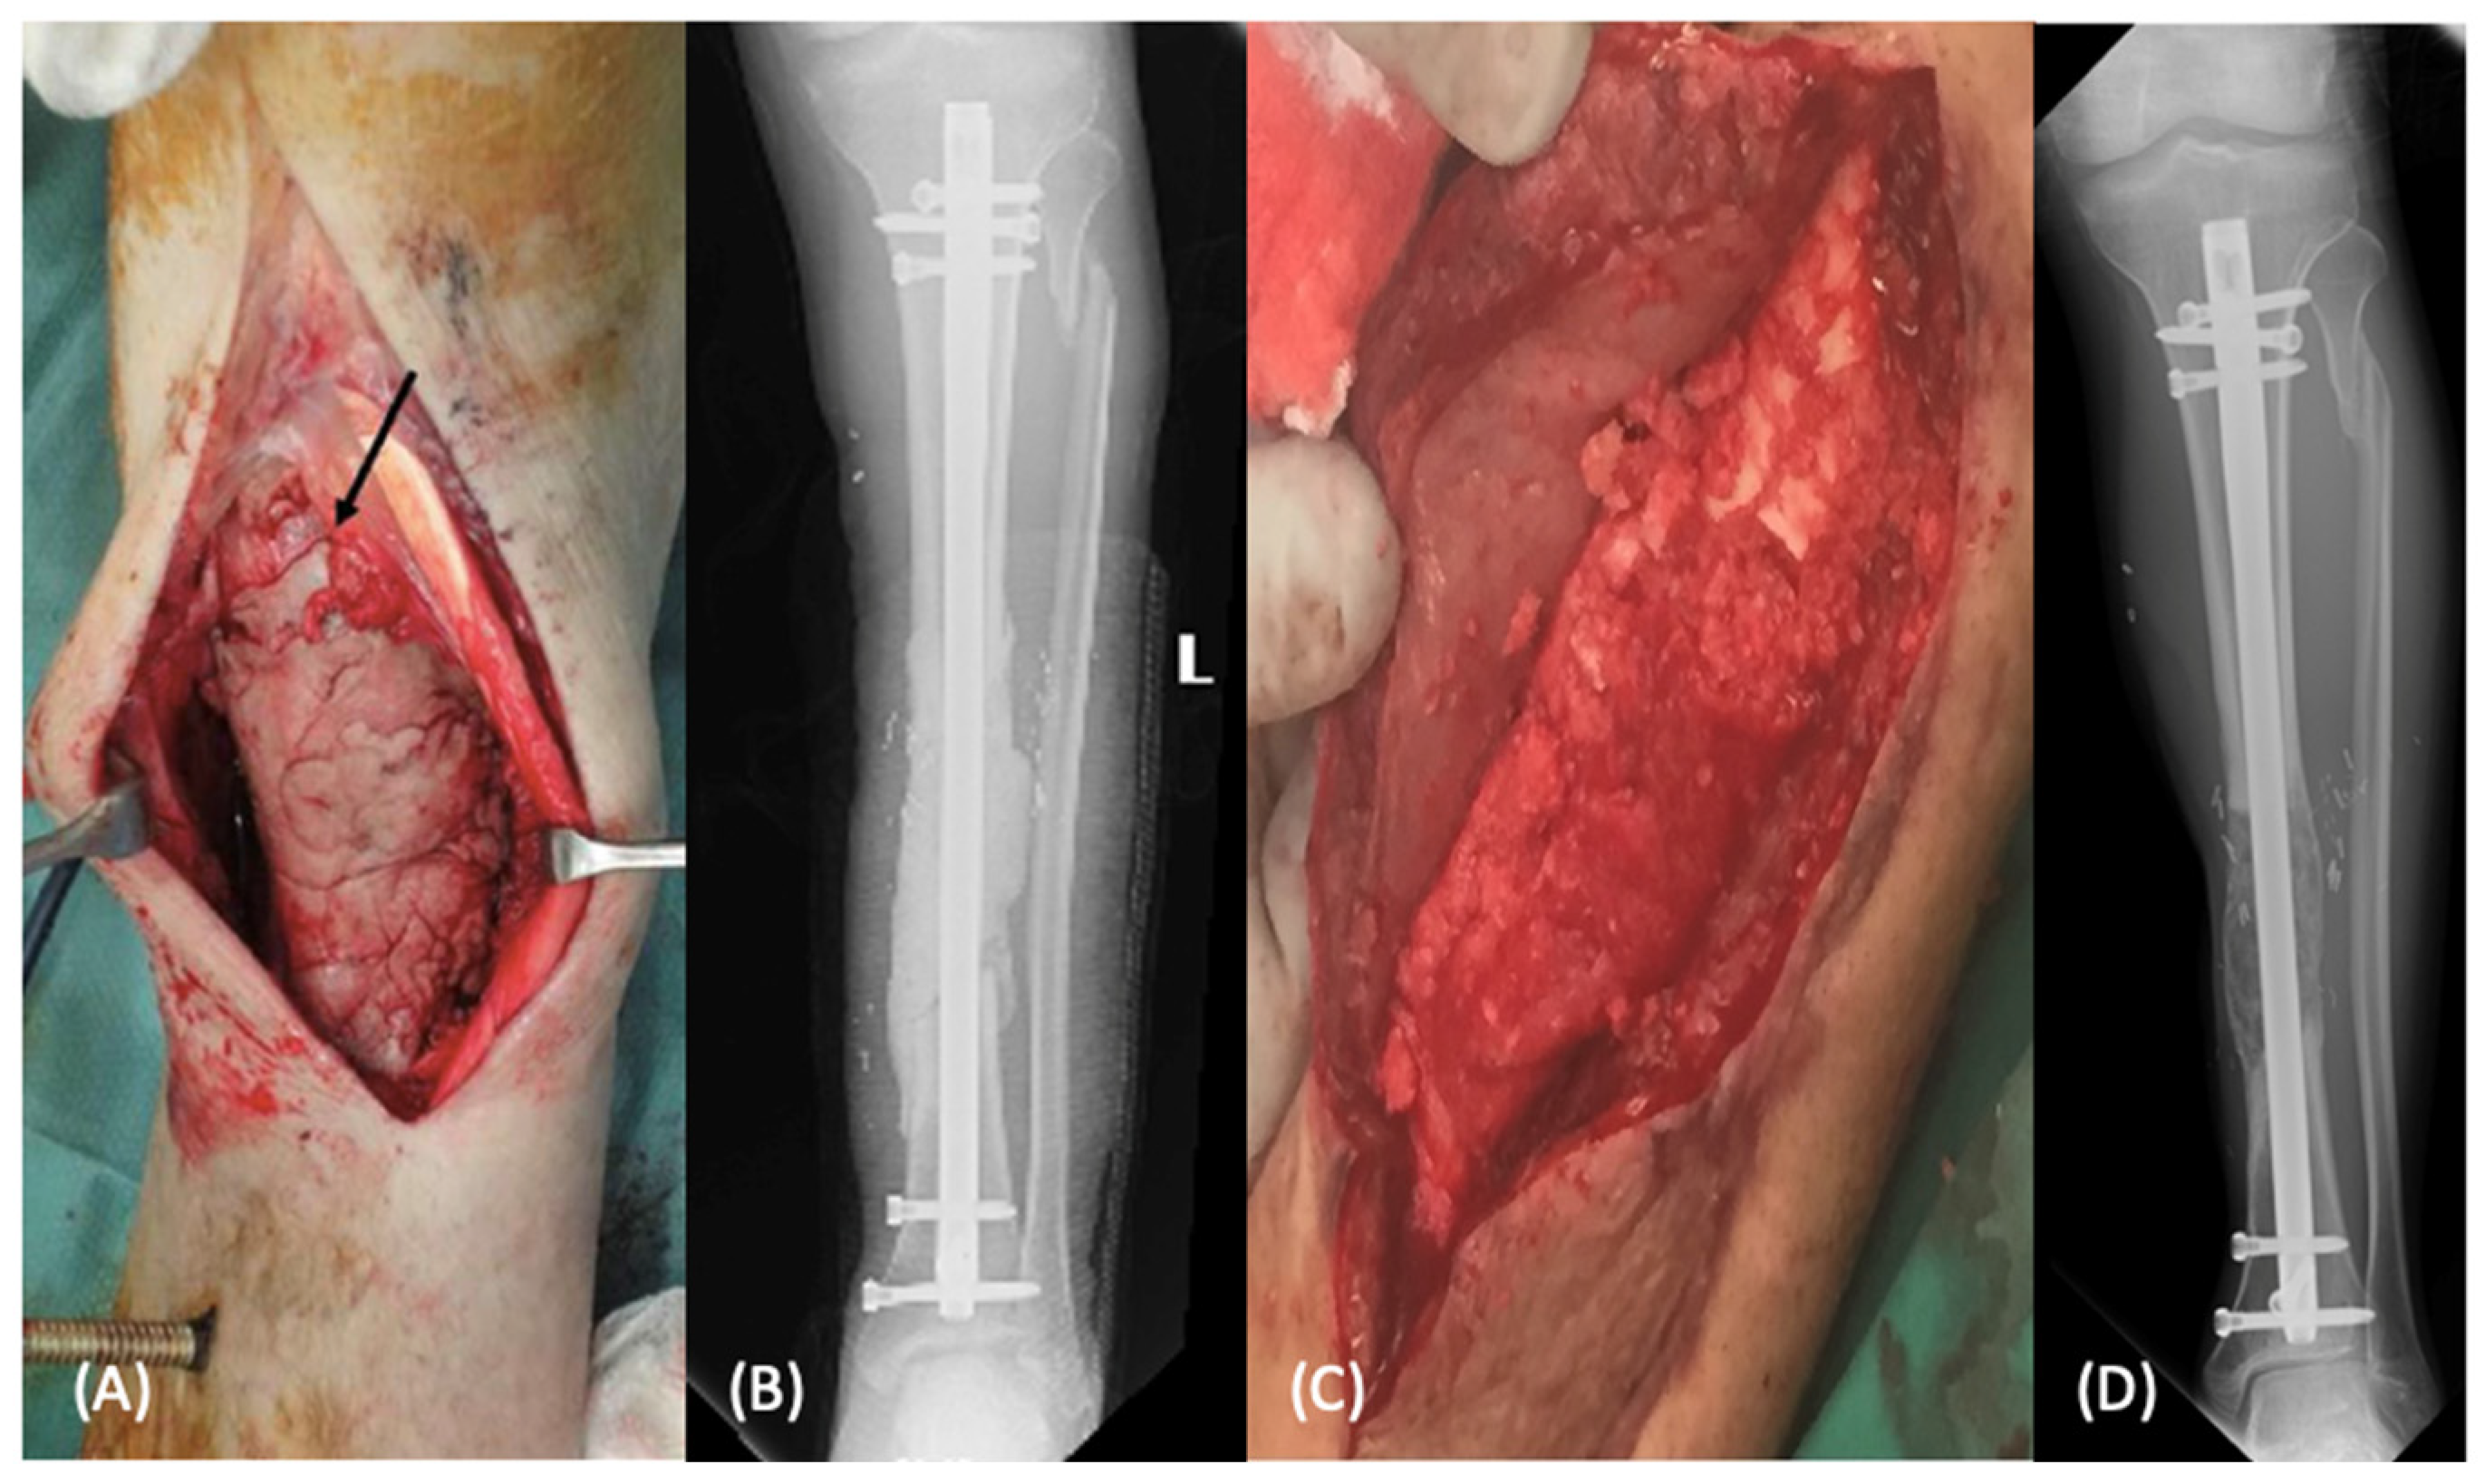

Figure 1.

Masquelet technique for diaphyseal tibial defect demonstrated in intraoperative photos of the antibiotic spacer placement (A) with post-operative radiographs (B). The patient underwent subsequent second stage autologous bone grafting into induced membrane (C) with post-operative radiographs seen in image (D).